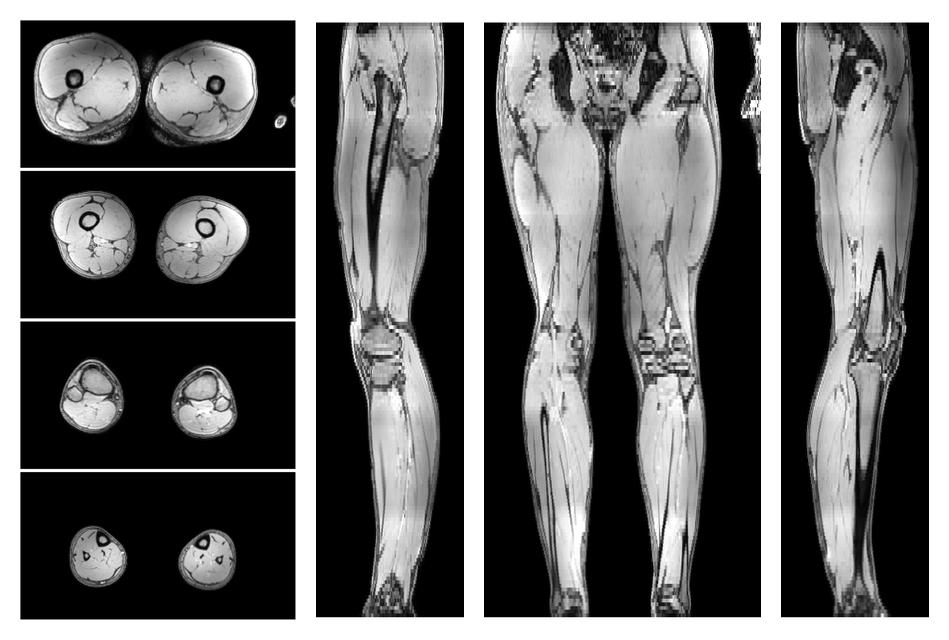

• SNR of the unweighted image

SNR distribution of the unweighted diffusion data.